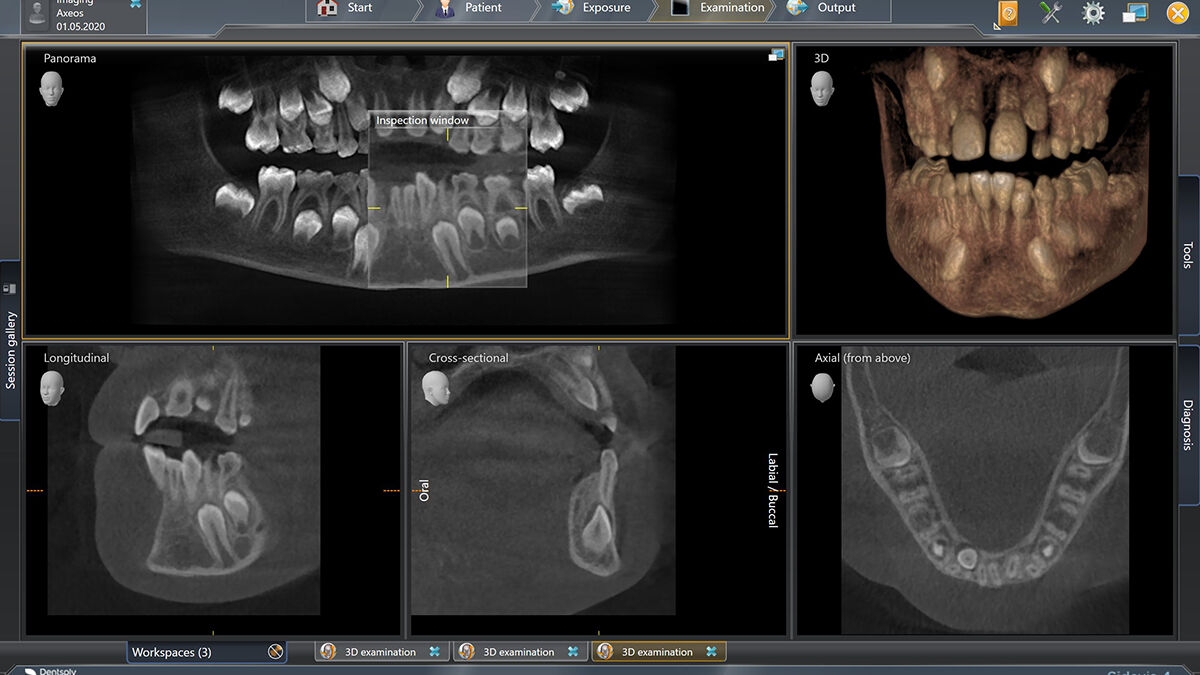

Exemplary 3D Images

Volume Ø 17 x 13 cm HD